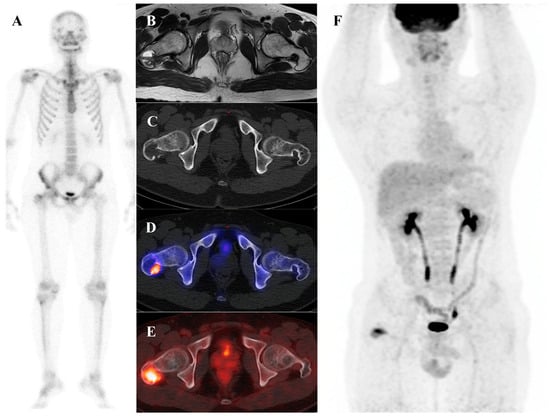

Osteoblastoma is a rare bone-forming tumor with a male predilection, most commonly occurring in the second to third decades of life. Its essential imaging features are a lytic lesion larger than 2 cm with well-defined borders and without permeation of the host bone. Osteoblastoma, a larger and more aggressive counterpart of osteoid osteoma, is histologically similar but shows greater growth potential with high vascularity and osteoblastic activity [66,67]. Consequently, they are intensely metabolically active and demonstrate markedly elevated [18F]FDG uptake on PET/CT [21,68]. Published reports document a wide range of high SUVmax in osteoblastomas, with averages around 3.2 in some series, individual cases reaching 6.2, and some spinal lesions exhibiting SUVmax as high as 16.0 [68,69,70,71]. This level of [18F]FDG avidity is well within the range of, and often exceeds that of, many malignant bone sarcomas. This significant overlap renders [18F]FDG PET incapable of reliably differentiating a benign osteoblastoma from a malignancy based on the intensity of uptake alone. The diagnosis relies on integrating the PET findings with the characteristic radiographic appearance and location. Figure 5 illustrates a case of osteoblastoma in the iliac bone, where bone scintigraphy, MRI, and SPECT/CT together demonstrated the characteristic features of this entity.

Figure 5.

A 38-year-old male with osteoblastoma of the left iliac bone. (A,B) Bone scintigraphy (posterior view) shows no abnormal perfusion on the blood pool phase, but focal increased uptake in the left iliac bone on the delayed phase. (C) T2-weighted fat-suppressed magnetic resonance imaging demonstrates an irregular sclerotic lesion with surrounding bone marrow edema at the left iliac crest near the sacroiliac joint. (D,E) Bone single-photon emission tomography/computed tomography reveals an osteolytic lesion with a sclerotic rim and focal increased tracer uptake.